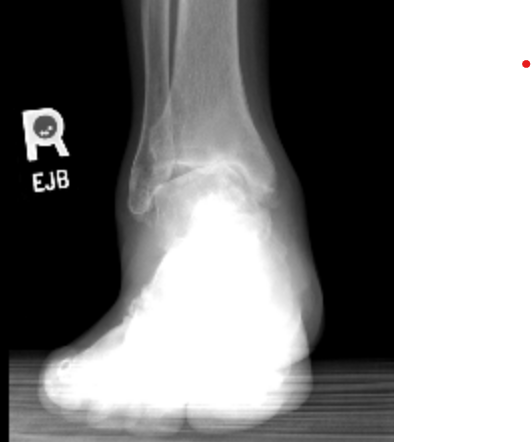

My right ankle was severe misaligned, which caused a great deal of pain with normal walking activities for years. Prior to meeting Dr. Cody, other orthopedic doctors told me that the only option was to have ankle fusion surgery. I was very reluctant due to the potential of losing much of the ankle flexibility. After the comprehensive assessment by Dr. Cody, she concluded that I was a suitable candidate for the total ankle replacement surgery instead. I am grateful for that advice. The surgery was extremely successful. I am now fully functional without any pain or loss of flexibility.